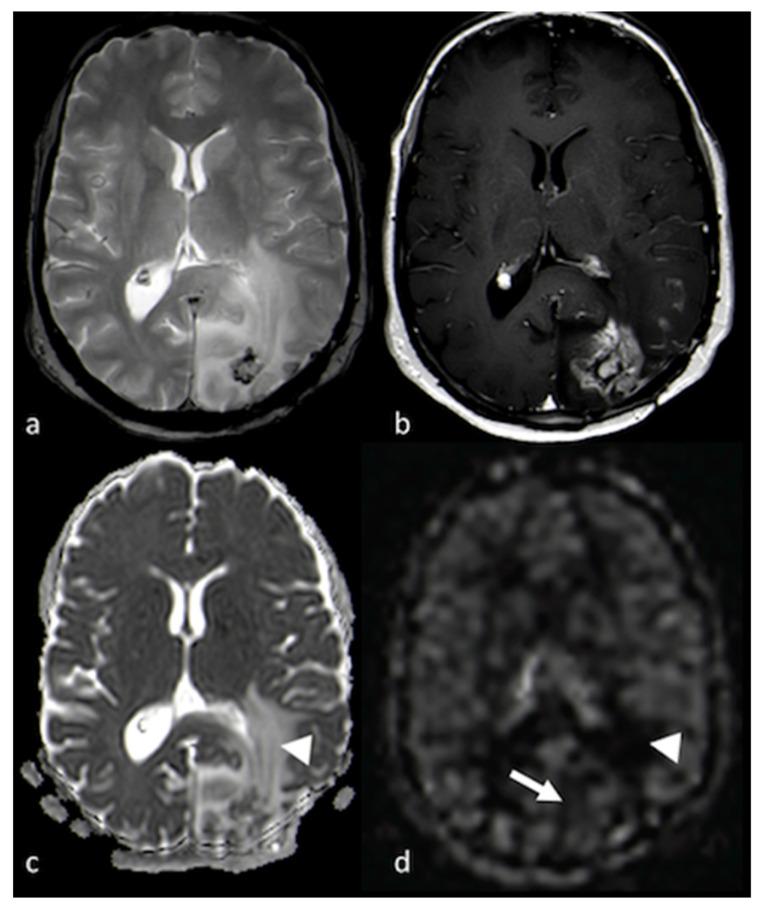

The non-enhancing peritumoral area (NEPA) is defined as the hyperintense region in T2-weighted and fluid-attenuated inversion recovery (FLAIR) images surrounding a brain tumor. The NEPA corresponds to different pathological processes, including vasogenic edema and infiltrative edema. The analysis of the NEPA with conventional and advanced magnetic resonance imaging (MRI) was proposed in the differential diagnosis of solid brain tumors, showing higher accuracy than MRI evaluation of the enhancing part of the tumor. In particular, MRI assessment of the NEPA was demonstrated to be a promising tool for distinguishing high-grade gliomas from primary lymphoma and brain metastases. Additionally, the MRI characteristics of the NEPA were found to correlate with prognosis and treatment response. The purpose of this narrative review was to describe MRI features of the NEPA obtained with conventional and advanced MRI techniques to better understand their potential in identifying the different characteristics of high-grade gliomas, primary lymphoma and brain metastases and in predicting clinical outcome and response to surgery and chemo-irradiation. Diffusion and perfusion techniques, such as diffusion tensor imaging (DTI), diffusional kurtosis imaging (DKI), dynamic susceptibility contrast-enhanced (DSC) perfusion imaging, dynamic contrast-enhanced (DCE) perfusion imaging, arterial spin labeling (ASL), spectroscopy and amide proton transfer (APT), were the advanced MRI procedures we reviewed.

肿瘤周围无强化区(NEPA)被定义为脑肿瘤周围T2加权成像和液体衰减反转恢复(FLAIR)成像中的高信号区域。NEPA对应于不同的病理过程,包括血管源性水肿和浸润性水肿。有人提出在实体脑肿瘤的鉴别诊断中,采用传统和先进的磁共振成像(MRI)分析NEPA,其显示出比MRI评估肿瘤强化部分更高的准确性。特别是,MRI对NEPA的评估被证明是区分高级别胶质瘤与原发性淋巴瘤和脑转移瘤的一种有前景的工具。此外,还发现NEPA的MRI特征与预后和治疗反应相关。本叙述性综述的目的是描述采用传统和先进MRI技术获得的NEPA的MRI特征,以便更好地理解它们在识别高级别胶质瘤、原发性淋巴瘤和脑转移瘤的不同特征以及预测临床结局和对手术及放化疗反应方面的潜力。扩散和灌注技术,如扩散张量成像(DTI)、扩散峰度成像(DKI)、动态磁敏感对比增强(DSC)灌注成像、动态对比增强(DCE)灌注成像、动脉自旋标记(ASL)、波谱分析和酰胺质子转移(APT),是我们所综述的先进MRI检查方法。